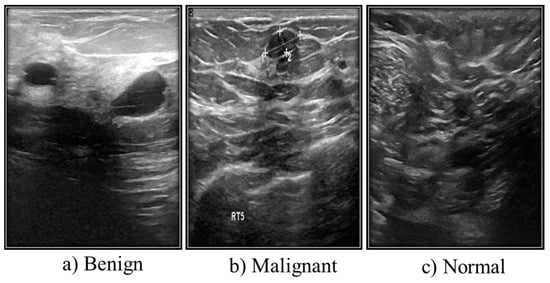

3.2. Ultrasound Images

| Case | Number of Images |

|---|---|

| Benign | 487 |

| Malignant | 210 |

| Normal | 133 |

| Total | 780 |